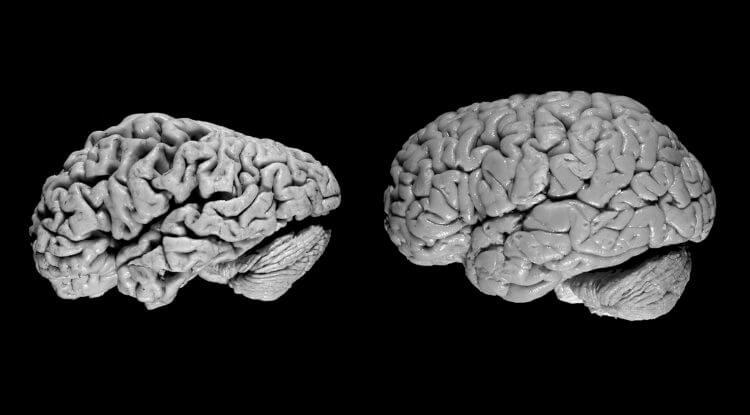

Сегодня в мире живут миллионы людей с болезнью Альцгеймера и другими формами деменции. У них сильно уменьшен объем серого вещества в головном мозге, но если с каждым поколением его количество будет увеличиваться само собой, люди будут страдать от деменции все реже. Судя по статистике, такая тенденция заметна уже сейчас — заболеваемость нейродегенеративными болезнями в США и Европе каждое десятилетие снижается примерно на 13%.

Мозг человека с деменцией (слева) и здорового человека (справа)

Ученые считают, что увеличение объема мозга у человека — это хорошая новость. По их мнению, благодаря этому в будущем люди будут меньше страдать от деменции. Так называется совокупность заболеваний, которые приводят к разрушению головного мозга и неспособности человека запоминать информацию, адекватно мыслить и так далее.Сегодня в мире живут миллионы людей с болезнью Альцгеймера и другими формами деменции. У них сильно уменьшен объем серого вещества в головном мозге, но если с каждым поколением его количество будет увеличиваться само собой, люди будут страдать от деменции все реже. Судя по статистике, такая тенденция заметна уже сейчас — заболеваемость нейродегенеративными болезнями в США и Европе каждое десятилетие снижается примерно на 13%.

В ходе предыдущих исследований было доказано, что у людей с большим объемом мозга болезнь Альцгеймера протекает гораздо легче. Это можно назвать весомым доказательством гипотезы «запаса мозга». Согласно ей, чем крупнее у мужчины или женщины мозг, тем дольше он будет сохранять способность запоминать информацию и мыслить — болезнь попросту будет разрушать мозг медленнее из-за его большого объема.